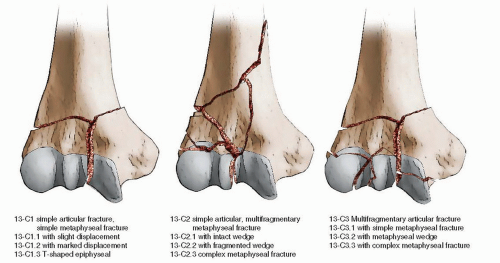

In children, many fractures can be treated with a cast, but some more severe fractures may need surgery, which involves repairing the fracture with temporary wires followed by casting. The growing areas of the elbow bones (growth plates) in a child are softer and can break with minor falls on a playground or off a trampoline. Special considerations should be made for fractures in children and the elderly. These injuries are very complex and typically require multiple plates to stabilize the broken bones. Distal humerus fractures often involve the joint and will require surgery, which involves repairing the fracture with plates and screws. This bone contains the entire joint surface of the elbow.

These fractures involve the portion of the humerus closest to the elbow joint. Complex fractures may also involve ligament injuries that need to be surgically repaired. Some more complicated fractures may require replacing the radial head with a metal implant if there are too many bony pieces. Complex fractures often require surgery with screws or a plate. Simple fractures can be treated with a brief period of immobilization with a splint or sling followed by moving the elbow to pain tolerance. The treatment for this fracture depends on the number and size of the bone fragments. The pain associated with these fractures is present on the outside (lateral) portion of the elbow and usually worse with forearm rotation. The radial head and neck, which are closest to the elbow, are important for rotation of the forearm (twisting from palm up to palm down). Radial head and neck fractures (see Figure 2) The main types of fractures are included below. In some severe cases, multiple bones may be broken at the same time. The location of the fractured bone is important to identify as this will determine the proper treatment and rehabilitation. The humerus starts at the shoulder, and the end (distal) part of it is in the elbow. The ulna also spans from the elbow to the wrist, but the head is in the wrist, and the cup-shaped part in the elbow is called the olecranon. The radius spans the length of the forearm from the wrist to the elbow, and the head and neck of the radius bone are inside the elbow joint. There are three main bones in the elbow (see Figure 1): the humerus, the radius, and the ulna.